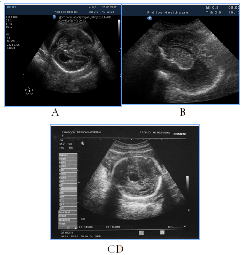

In 5fetuses with severe prolonged course of placental dysfunction we antenatally detected modified insular complex with anomalously broad lateral (Sylvian) sulcus as a signs of abnormal gyration and sulcation (Figure 7). US images of cortical dysplasia in our study were associated with fetal intrauterine growth retardation (IGR), Oligohydramnios, metabolic acidosis and neuro infection. These fetuses had adverse GPO (3cases) and extremely unfavorable CPO (2cases) (Figure 8).

Figure 7NSG of two fetuses of the same gestational age (29 GW) with normal brain image (A), also with a signs of cortical dysplasia (B).

Figure 8Abnormal image of the cerebral cortex as a manifestation of abnormal neuronal migration in two fetuses in 3rd trimester of pregnancy, fetal US and neonatal MRI.

NSG of two fetuses of the same gestational age (29 GW) with normal brain image (A), also with a signs of cortical dysplasia (B).

Figure 8 Abnormal image of the cerebral cortex as a manifestation of abnormal neuronal migration in two fetuses in 3rd trimester of pregnancy, fetal US and neonatal MRI. A, B) 30GW, cortical dysplasia, the type of neuronal heterotopia and pachygyria, long-term violations as severe epilepsy and retardation of development in catamnesis. C,D,E) 29 GW, cortical dysplasia in the fetus with significant IGR and antenatal distress, postnatal transmantian dysplasia, lissencephaly and presilvian polymicrogyria that clinically was accompanied by hypotension and child neurological disabilities.